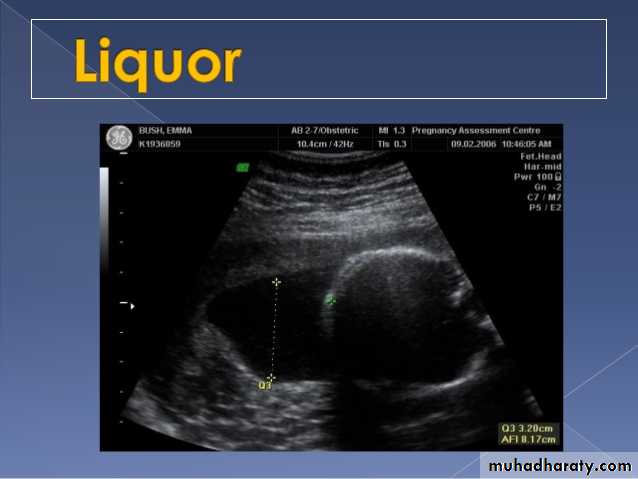

Poly hydraminous

Poly hydraminos refers to a situation where the amniotic fluid volume is more than expected for gestational age.

It is generally defined as:

amniotic fluid index (AFI) > 25 cm

largest fluid pocket depth (maximal vertical pocket (MVP)) greater than 8 cm

overall amniotic fluid volume larger than 1500-2000 cc3